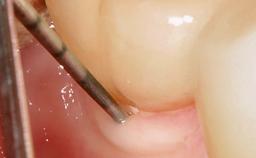

In this case, Nicola Zitzmann describes the sudden loss of a previously well-osseointegrated implant that had been in healthy function for 5 years. The case includes recommendations for occlusion and function of implant restorations. A 74-year-old patient had received implant-fixed dental prostheses in the maxilla in 2008, and in the right mandible three years later. His tooth loss was mainly related to recurrent caries associated with hyposalivation as a potential side effect of his cholesterol-lowering medication.